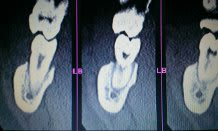

Voici le scanner d'un patient chez qui l'extraction des dents 47 et 48 est indiquée. Etant donné le positionnement de ces dents par rapport au nerf, j'aurais aimé avoir vos différents points de vue quant à la meilleure solution thérapeutique à adopter.

Il y a un risque de compression legere du V3 sans plus. Bien separer les racines de 48 et voir avec 47, si elle sort facilement sinon separer aussi apres lambeau 47-48 et fraisage osseux vestibulaire pour facilier une extraction dans sens linguo vestibulaire.

Pas d'indication de coronectomie pour moi.

+1 pour le risque de paresthésies transitoires. pas de risque de lésion irréversible si chirurgie bien menée.

Dans un cas comme celui-là, où les apex semblent être en contact direct avec le canal alvéolaire inférieur, il n'y a donc pas de compression systématique du nerf provoquée par l'hémorragie de l'extraction, avec les conséquences réversibles ou non que l'on connait?